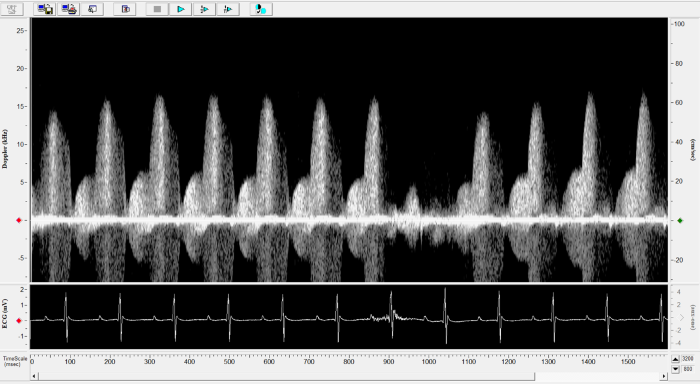

Carotid

Carotid Image. Image Credit: Scintica Instrumentation Inc.